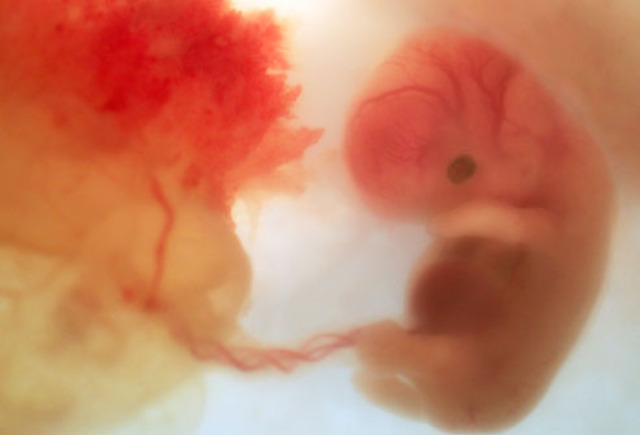

• Month 2 Baby

Month 2 Baby

Size: about 1/4 inch (6 mm) long as month begins.

Face, eyes, ears, and limbs shape.

Bone begin to form.